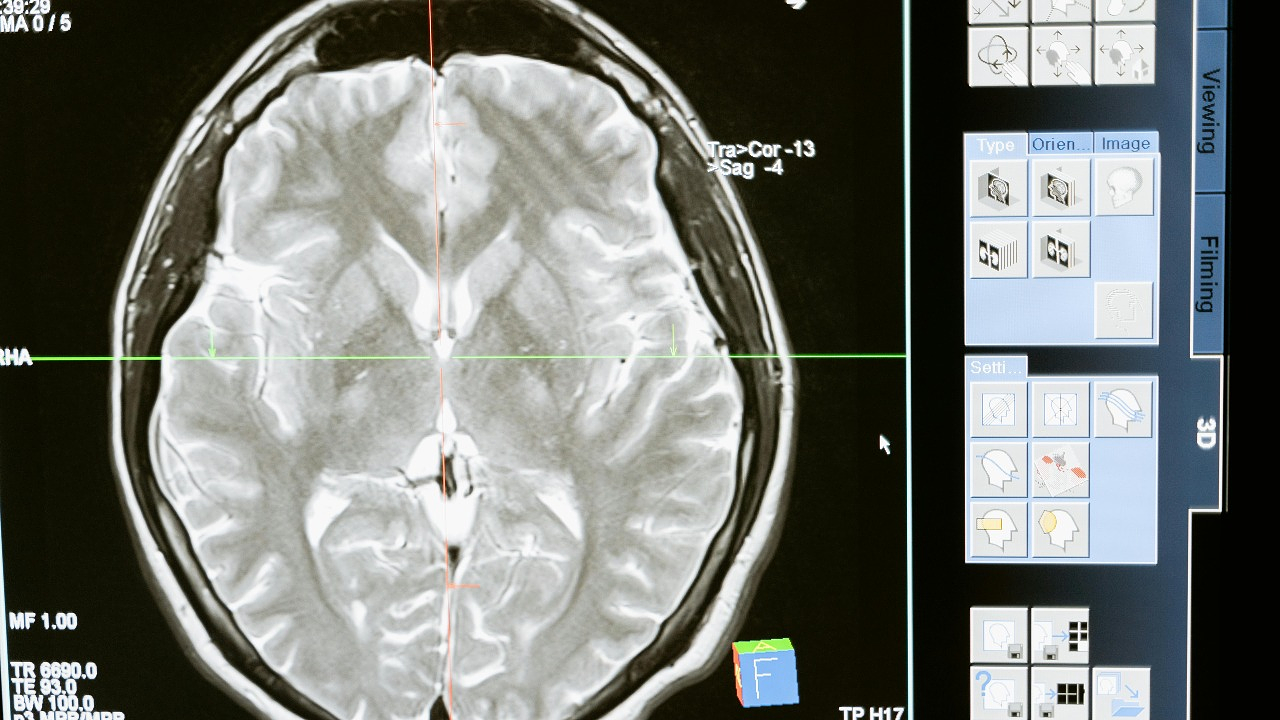

Анализу предстоит пройти финальный этап – валидацию и проверку. В нём примут участие 8000 пациентов. Всего 10 капель крови позволяют обнаружить до 12 распространённых видов рака – лёгких, желудка, простаты, пищевода, печени, мочевого пузыря, яичников, кишечника, поджелудочной железы, молочной железы, а также саркому и опухоль мозга.

Тест основан на поиске в крови микрочастиц ДНК, которые выделяются опухолью задолго до появления симптомов. На предыдущем этапе исследование уже охватило 20 тысяч человек. Испытание совпало с открытием лаборатории Bowelbabe – в память о журналистке и активистке Деборе Джеймс, которая умерла от рака кишечника в 2022 году в возрасте 40 лет. Её фонд помог финансировать проект.